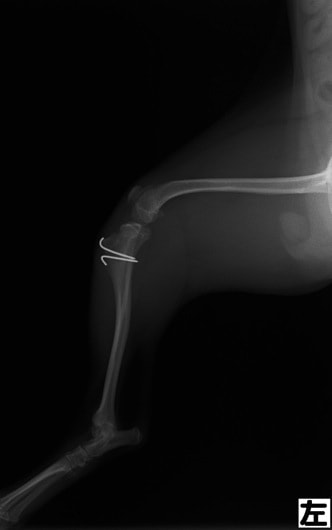

■ 症例24 キャバリア 7か月

左右膝蓋骨内方脱臼(左:グレードⅣ 右:グレードⅢ)

以前から左右後肢の跛行が認められ、整形外科学的検査・レントゲン検査により左右の膝蓋骨脱臼が認められた。症状が重度である左膝の膝蓋骨脱臼整復術を行った。外科手技は縫工筋及び内側広筋の解放、脛骨粗面の外側転位、滑車ブロック形造溝術、内外側関節方の縫縮を実施した。術後一か月時点で、左の膝蓋骨は安定しており経過は良好である。

本症例は成長期における重度の膝蓋骨脱臼であり、術後の再発の可能性もあるため、経過をしっかりと観察していく必要がある。また、今回手術を実施していない右膝に関しても経過を観察し、手術を検討していくこととする。